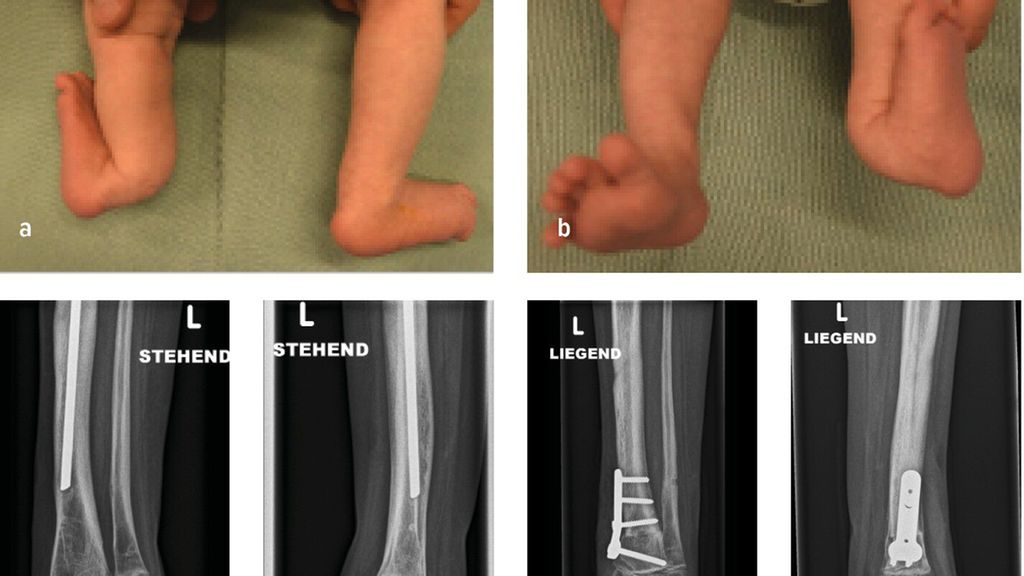

Die genaue Epidemiologie und Pathogenese des posteromedialen Bowings, auch bekannt als Crus valgum recurvatum, sind unbekannt. Einzelne dokumentierte Fälle in der Literatur lassen jedoch darauf schließen, dass es sich hierbei um eine sehr seltene Fehlstellung des Unterschenkels handelt, die vor allem die linke Extremität betrifft.15,16 Die Biegung der Tibia nach hinten und zur Körpermitte beträgt zwischen 25 und 70° und tritt typischerweise am Übergang vom mittleren zum distalen Drittel auf. In ausgeprägten Fällen kann die Fehlstellung bis zu 90° betragen. Der Fuß des Neugeborenen kann in schweren Fällen auf der Schienbeinkante zu liegen kommen. Bildlich repräsentiert dies der Fall eines 6 Wochen alten Mädchens mit posteromedialem Bowing der linken unteren Extremität mit typischer Biegung am Übergang vom mittleren zum distalen Drittel. Hier kommt der Fußrücken an der Unterschenkelkante zu liegen (Abb.3a,b). Differenzialdiagnostisch ist dabei an eine Calcaneo-valgus-Fehlstellung des Fußes zu denken.16 Eine spontane Rückbildung der Fehlstellung wird im Laufe des Wachstums bis zum 4.–5. Lebensjahr beobachtet.15 Konservative Maßnahmen beschränken sich initial auf sanfte Fußmassagen des Neugeborenen. In schweren Fällen kann eine graduelle Gipsredression eingesetzt werden.14

Abb. 3: 6 Wochen altes Mädchen mit posteromedialem Bowing der linken unteren Extremität (a+b) sowie postoperative Bildgebung

Verbleibende Fehlstellungen, insbesondere Rekurvation der Tibia, Beinlängendifferenz, Torsionsfehler oder Valgusfehlstellung der Tibia oder des Sprunggelenkes, bedürfen einer chirurgischen Intervention. Die dysplastische keilförmige Wachstumsfuge an der distalen Tibia begünstigt in einigen Fällen die Valgusfehlstellung im Sprunggelenk. Im Rahmen der Bildgebung präsentiert sich in dieser Abbildung ein 6 Jahre altes Mädchen mit einer selten auftretenden verbleibenden Valgusfehlstellung im Sprunggelenk bedingt durch eine dysplastische keilförmige Wachstumsfuge bei Z.n. Korrektur und Verlängerung mittels Fixateur externe und Stabilisierung mit intramedullärem Nagel (Abb.3c,d). Als chirurgische Therapien stehen hierfür die Wachstumslenkung an der distalen Tibia oder akute (supramalleoläre Korrekturosteotomien (Abb.3e,f) bzw. graduelle (externer Fixateur) Korrekturen zur Verfügung. Verbleibende Beinlängendifferenzen können durch eine Wachstumsbremsung der kontralateralen Seite bei geringer Beinlängendifferenz oder mittels gradueller Distraktionsosteogenese (externer Fixateur) therapiert werden.14,16,17